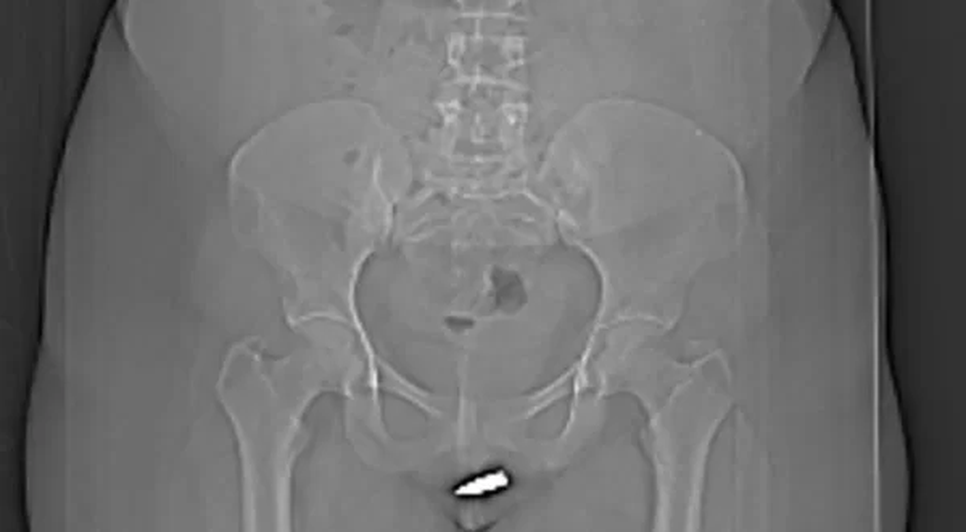

A jovem foi levada às pressas para o Hospital Erdoğan, na capital do país, queixando-se de fortes dores na vagina. Exames de tomografia computadorizada mostraram que o projétil de 2 centímetros atravessou a vulva da paciente e ficou alojado dentro do clitóris dela.

O projétil foi removido cirurgicamente sob anestesia local. Os médicos destacaram que o procedimento precisou ser feito com cuidado extra para não danificar a uretra e a região pélvica da paciente. A jovem teve alta no dia seguinte, depois de uma avaliação médica constatar que ela não sofreu complicações devido à bala.